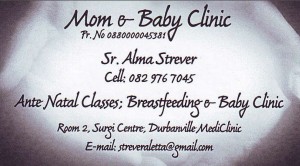

Alma PreNatal2